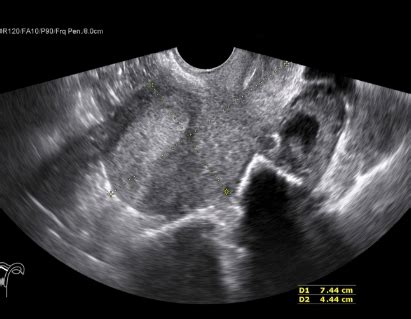

When you’re searching for ultrasound imaging near me , you might be curious about the different types. The most common type is the transabdominal ultrasound , where the probe is moved over the abdominal wall, as we’ve discussed. This is often used for evaluating organs like the liver, kidneys, and gallbladder, and is standard for pregnancy scans after the first trimester. Then there’s the transvaginal ultrasound , typically used for gynecological and early pregnancy assessments. In this case, a smaller, covered probe is inserted into the vagina, providing a much closer and more detailed view of the uterus and ovaries.

For looking at breasts, a breast ultrasound is often used, either as a follow-up to a mammogram if something suspicious is found, or as a primary imaging tool for younger women or those with dense breast tissue. Doppler ultrasound is a specialized type that not only shows blood flow but also measures its speed and direction. This is crucial for detecting issues like blood clots, narrowed arteries, or problems with blood flow to organs. Vascular ultrasounds, which assess arteries and veins throughout the body, heavily rely on Doppler technology.

Other specialized ultrasounds include echocardiograms (ultrasound of the heart), thyroid ultrasounds , scrotal ultrasounds , and ultrasounds used to guide procedures like biopsies (known as interventional or procedural ultrasounds ). Each type uses the same basic principle of sound waves but is tailored with specific probes and techniques to visualize particular areas of the body with maximum clarity. The type of ultrasound you need will depend entirely on your medical condition and what your doctor is trying to diagnose or monitor.